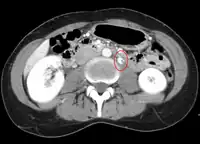

Compression of the left renal vein (marked by the arrow) between the superior mesenteric artery (above) and the aorta (below) due to nutcracker syndrome